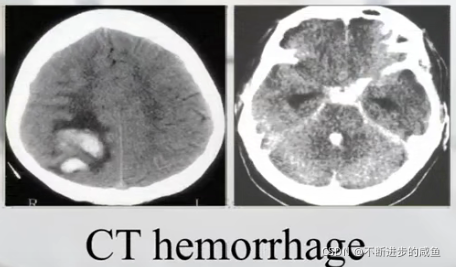

(1)CT图像: 骨结构、组织结构(不太清晰)